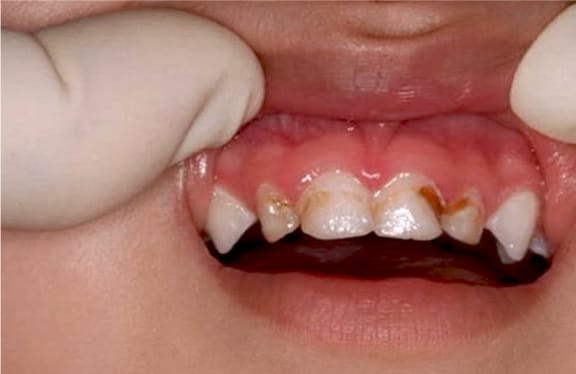

Early Childhood Caries

Childhood cavities, also now known as "Early Childhood Caries" is an aggressive form of caries that occurs in infants and very young children. It is typically associated with prolonged consumption of liquids containing sugar and affects initially the top front teeth, later spreading to other "baby teeth." Because of the aggressive nature of this disease, early intervention is necessary.

The American Academy of Pediatric Dentistry (AAPD) and the American Academy of Pediatrics (AAP) recommend that ALL children should see a dentist before age one.

Baby Bottle Tooth Decay

Baby bottle tooth decay or syndrome is a form of tooth decay that can destroy the teeth of an infant. This decay may even enter the underlying bone structure, which can hamper development of the permanent teeth. The teeth most likely to be damaged are the upper teeth.

Baby bottle decay is caused by frequent and long exposure of a child's teeth to liquids containing sugar such as milk, formula, fruit juices, pop and other sweetened liquids. These liquids fuel the bacteria in a child's mouth, which produces acids that attack enamel.